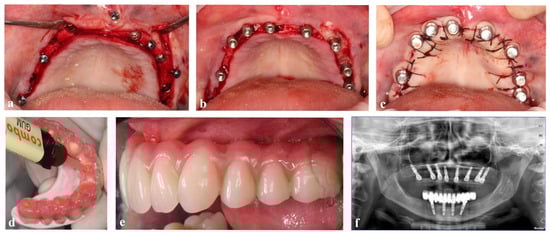

Figure 2 illustrates the surgical procedures for implant placement and prosthetic load through the CLIKSS technique.

Figure 2. Representative intraoral images of guided implant placement in an edentulous mandible. (a) Minimally invasive guided implant placement using the flapped approach; (b) connection of conometric straight and parallel abutments of the same height; (c) sutured soft tissues along with conometric coupling of the abutments with prosthetic caps. The patient leaves the office with temporary polyetheretherketone (PEEK) caps to protect abutments and a provisional prosthesis or a three dimensional (3D)-printed tray (Effegi Brega Srl, 29010 Sarmato, Italy); (d) the following day, the definitive prosthesis (Toronto Bridge) was attached, filling the space between the cap with composite resin, checking the occlusive fit, and polymerizing for a few minutes; (e) clinical view of the definitive prosthesis (Toronto bridge); (f) postoperative orthopantomography (OPT).